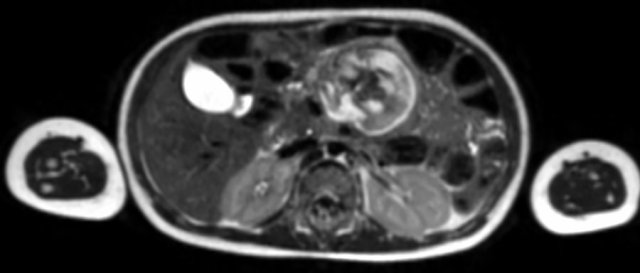

Image

Nephroblastoma of the left kidney in a three-year-old boy. The remnant of the kidney is draped over the tumor (“claw sign” arrow). The tumor is rather homogeneous with some cystic areas.

Continue with the MRI.

Nephroblastoma of the left kidney in a three-year-old boy. A bilobar tumor is present in the interpolar region. There is a dilated calyx in the upper pole (arrow).